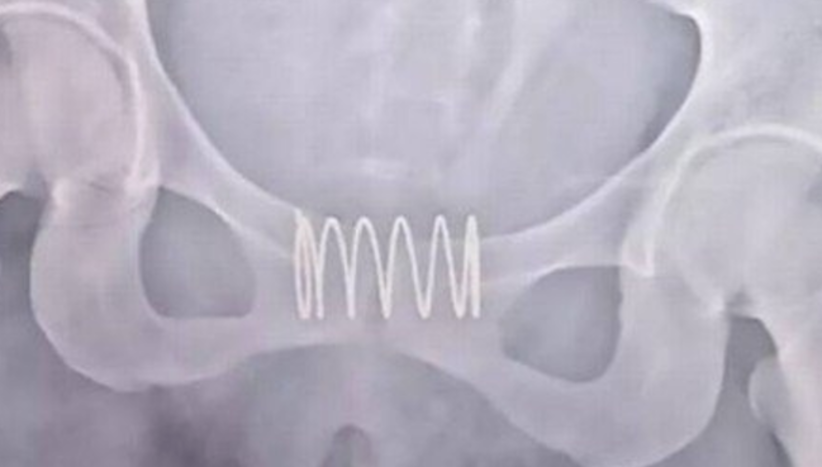

Ainda segundo o Extra, Porém a paciente chegou exatamente grávida ao hospital, no fim de julho. Para ser mais preciso, ela estava no quinto mês de gravidez. Um exame de imagem fez a descoberta da presença da mola na vagina.

A mola teve que ser cirurgicamente removida - aro por aro. O procedimento demorou 40 minutos, de acordo com o site "Unilad".